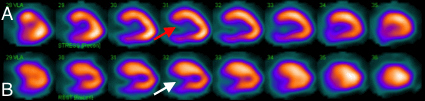

Estudio de perfusión miocárdica con 99mTc-MIBI en fases post-estrés físico y reposo (imágenes únicamente del eje largo vertical). A. Imágenes post-estrés en donde se observa aumento del volumen de la cavidad ventricular (flecha roja). B: Imágenes de reposo en el que se observa menor volumen de la cavidad ventricular (TID=1,28).

Ante estos hallazgos, se decidió realizar estratificación de riesgo mediante gammagrafía de perfusión miocárdica Gated-SPECT (estudio tomográfico sincronizado con electrocardiograma) con 99mTc-MIBI (dosis total 24 mCi) bajo protocolo de esfuerzo físico y reposo de 2 días. Las imágenes evidenciaron hipocaptación moderada en los segmentos basal y medial de las caras inferior e inferolateral del VI y en el segmento medial de la cara anteroseptal en el estrés, con reversión completa en el reposo. El resultado fue catalogado como isquemia inducida en los segmentos mencionados (figura 1), a lo que se asoció dilatación ventricular durante el estrés con TID (dilatación isquémica transitoria) calculada en 1,28 (valores considerados normales < 1,19) (figuras 2 y 3), fracción de eyección en el reposo de 57% que cayó a 40% post-estrés y deformidad parcial del septum basal.